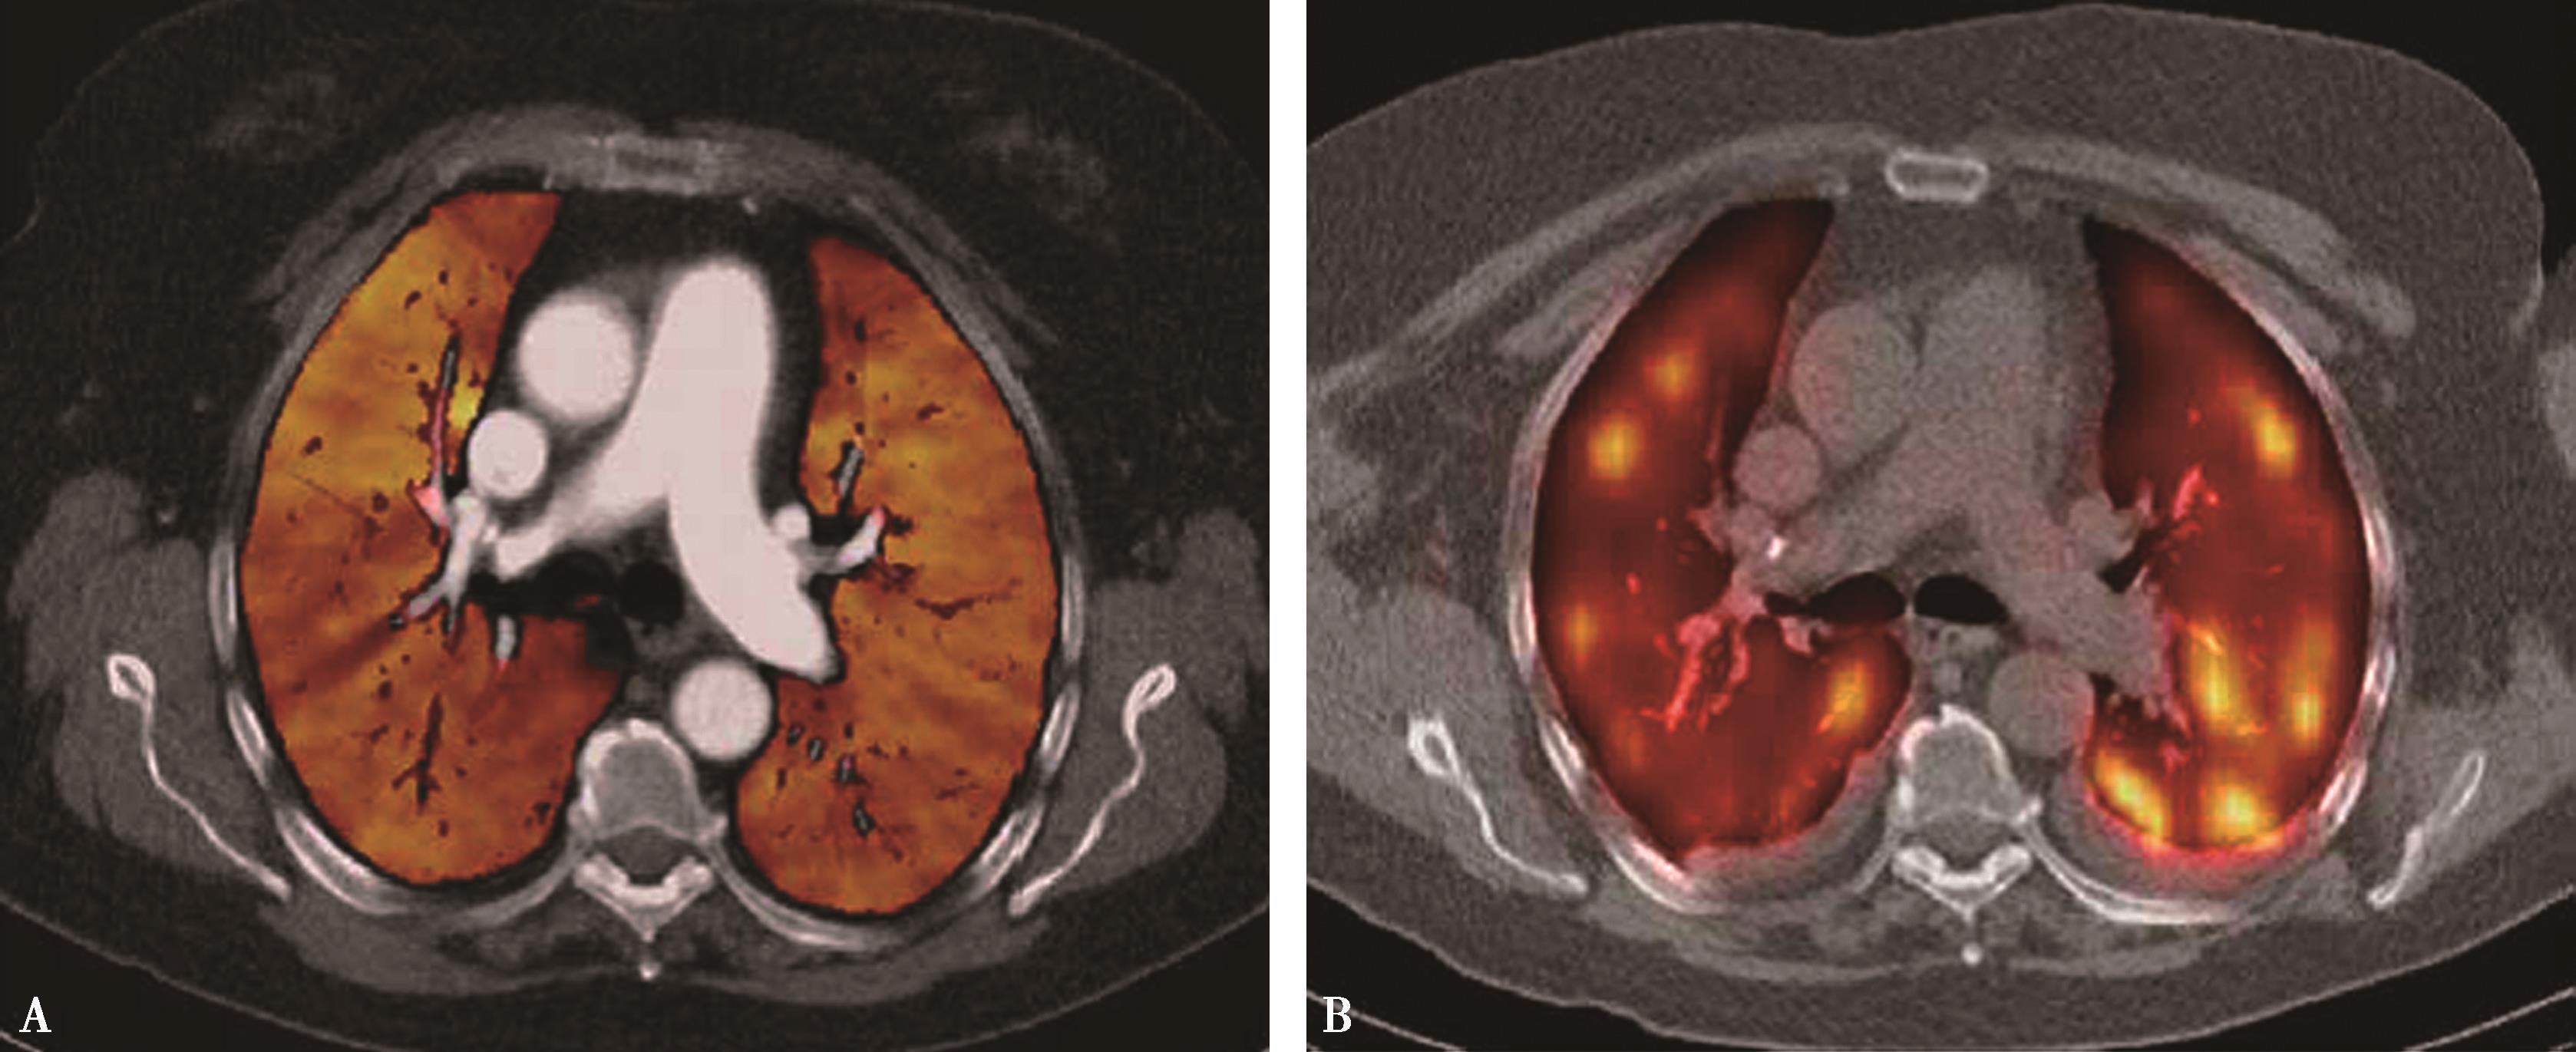

图8-3-5 肺栓塞双能CT肺灌注成像(DELPI)

CTPA显示左肺舌叶段-亚分段、下叶内前基底段-亚分段未显影(A↑),灌注扫描示相应肺段灌注缺损(B↑),明确左肺舌叶段-亚分段、下叶内前基底段-亚分段肺栓塞诊断

图8-3-6 肺栓塞双能量CT能谱成像

A.右肺下叶外基底段栓塞(↑);B.能谱成像得到肺碘基物质图,梗阻肺段呈低灌注,清楚反映栓塞分布、程度(↑)